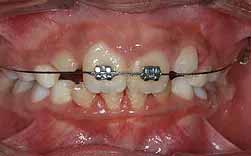

Um diastema interdentário é um espaço exagerado entre as coroas de dois dentes, na sequência normal de erupção. A sua origem pode ser:

Os diastemas devidos à diminuição da largura das coroas dos incisivos laterais superiores ou a um freio fibroso, só devem ser tratados após a erupção dos 2º molares definitivos, aos 13 anos.